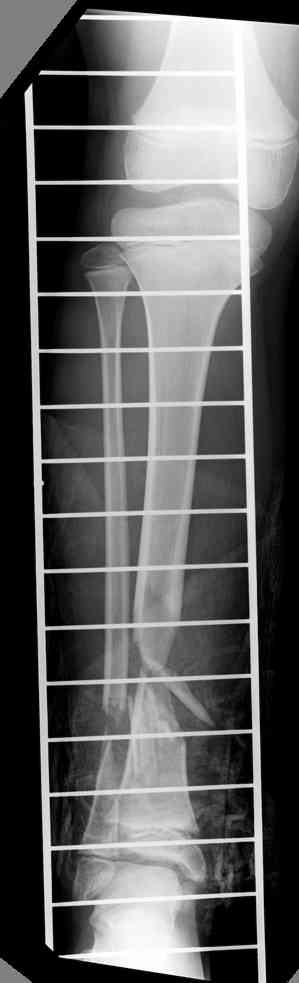

-->> дистальный фрагмент слишком короткий, меньше 2 см, нет места для интрамедуллярного штифта, в отличии от пациента Др. Иванова (прекрастный результат!).

Another choice is simply perform shortening + posterior angulation with Ilizarov or TSF , than gradual correction of the angulation.After all apply third ring on the proximal tibia and start lengthening.

We had recently similar case in 14 years old boy with 45 mm bone defect after open tibial fracture.Boy doing excellent .This technique is not new, Sasha Lerner did it in Rambam , Rozbruch wrote also.

> Another choice is simply perform shortening + posterior angulation

> with Ilizarov or TSF , than gradual correction of the angulation.

Действительно, если есть длинная косая линия на проксимальном отломке, это жалко будет не использовать. Можно сделать коррекцию угла не обратным разведением фрагментов, а оставить их в контакте, и сделать кортикотомию проксимальнее на 2-3 см. Можно и сейчас отсечь такой фрагмент и транспортировать его с разворотом. Наверно, вариант с ангуляцией более технологичен.